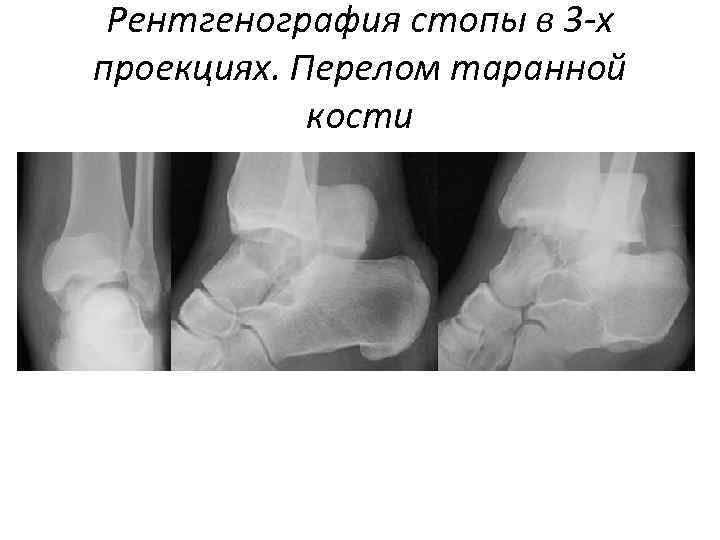

Рентгенография стопы в 3 -х проекциях. Перелом таранной кости